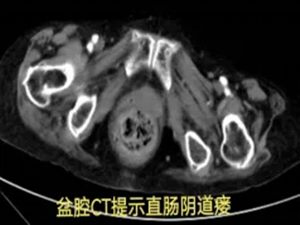

在积极止血过程中,团队发现出血并非单纯的直肠肛门问题,怀疑可能合并阴道瘘。初步处理后,患者被转入胃肠甲状腺外科进一步诊治,最终确诊为直肠阴道瘘并局部感染出血。

然而,真正的挑战才刚刚开始:患者20多年前曾接受直肠肿瘤手术,此次手术方案的制定难度陡增。高龄、既往直肠癌手术史、阴道瘘感染、凶猛的出血——其中任何一项单独出现,都已属高危;此刻,却全部叠加在一起。